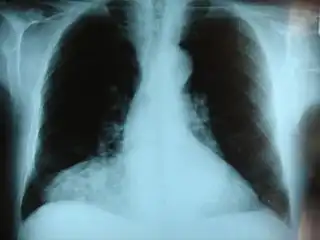

Radiografía frontal del pecho mostrando una hernia de Morgagni. | ||